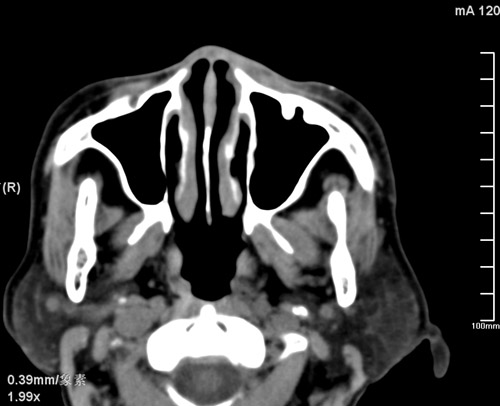

标题: CT17755:女,74 左鼻旁肿胀半年,临床以左上颌窦旁占位行CT [打印本页]

标题: CT17755:女,74 左鼻旁肿胀半年,临床以左上颌窦旁占位行CT

ct考虑鼻前庭囊肿 或鼻翼基底部慢性炎症,左上颌窦少许炎症 请指教

1)考虑左侧鼻前庭囊肿并感染。2)双侧上颌窦炎。

左侧鼻前庭囊肿并感染。双侧上颌窦炎。支持